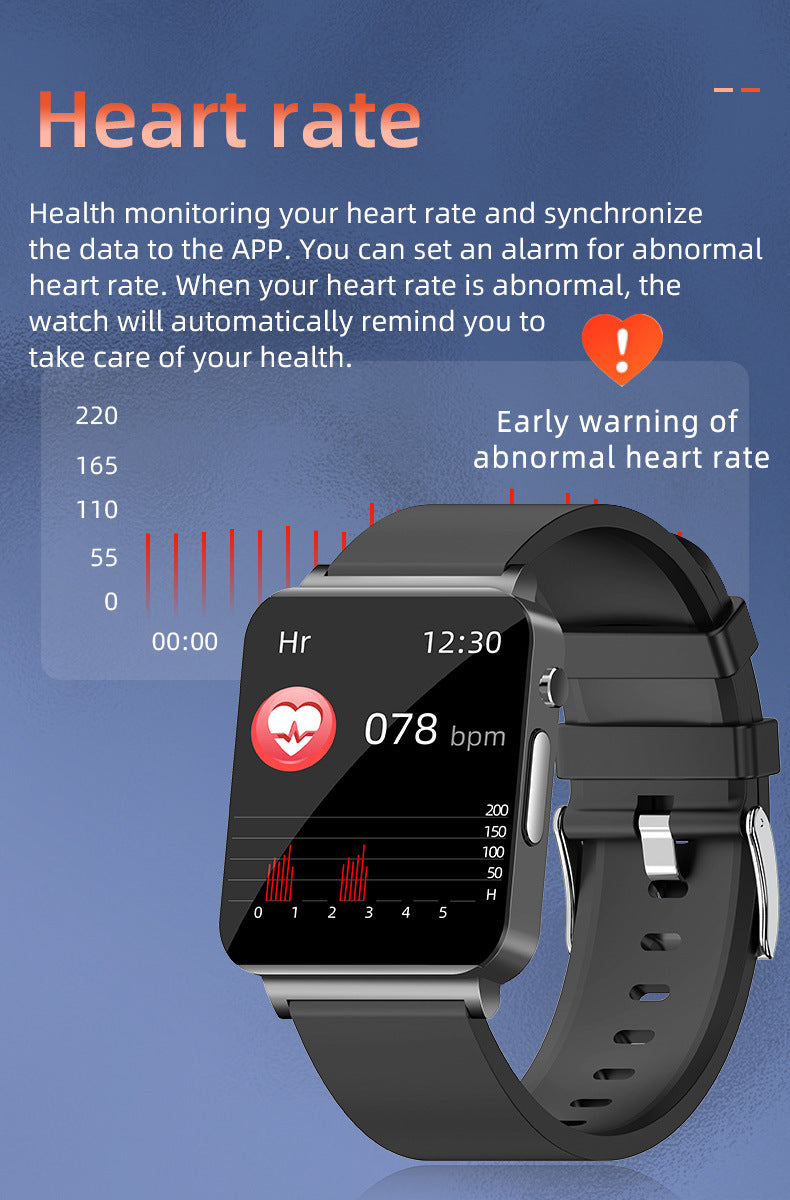

KS03 Smart Watch Heart Rate Blood Glucose Blood Oxygen ECG Monitoring

KS03 Smart Watch Heart Rate Blood Glucose Blood Oxygen ECG Monitoring

€74,95KS03 Smart Watch Heart Rate Blood Glucose Blood Oxygen ECG Monitoring

€74,95 -